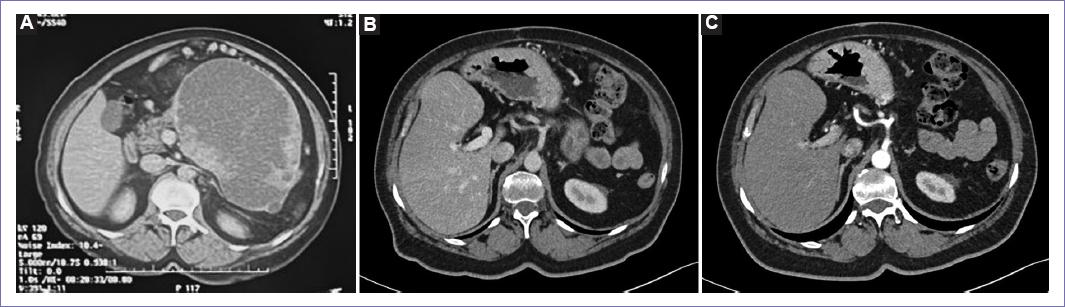

Onset 1 year before diagnosis with intermittent abdominal pain, abdominal distension, early satiety, nausea and vomiting, weight loss of 8 kg in 2 months, reason for which she attends to receive medical attention in a private setting where a CT scan is performed finding a pancreatic giant septate cyst heterogeneous lesion being referred to our institution where it was studied and scheduled for surgery (Fig. 1).

CT April 2023: Post-surgical changes at the pancreas level with absence of the body and tail, without lesions or masses in the surgical bed. Changes due to splenectomy without obvious lesions, but with residual fatty striation. This study shows no evidence of recurrence or new lesions in the surgical bed of the known primary tumor (Fig. 5).

Figure 5 Tac scan: A: previous to surgery, May 2021. B: two-years after surgery, August 2023. C: three-years after surgery, May 2024.

CT AUGUST 2023: No changes. Shows no evidence of recurrence or new lesions. Laboratory results 12.08.23: Normal, CA 19-9: 3.0.